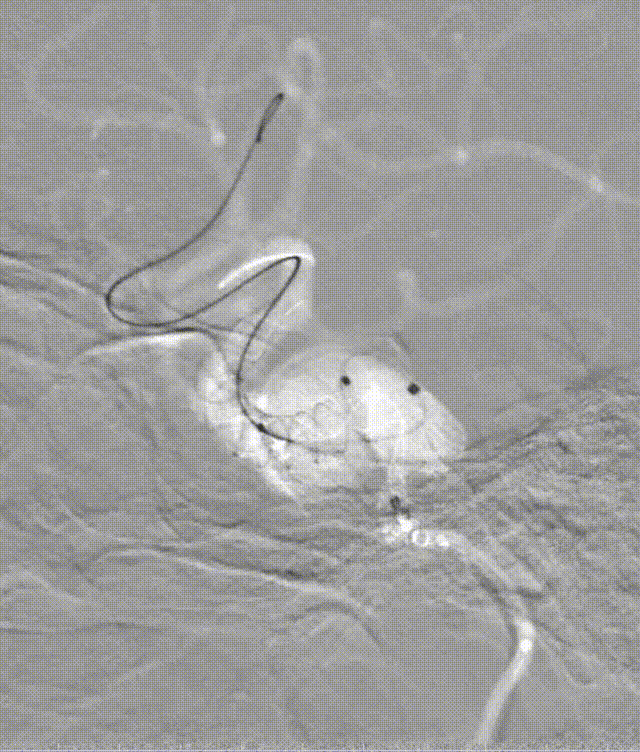

路图下先释放4.0*25mm 密网支架完全覆盖瘤颈,用J型微导丝予以支架内按摩。术中 Vaso CT证实支架打开贴壁良好。

动脉长鞘怎么置入深谋远路 | 千人皆翘首,万唤今始来——国内首款7F长鞘在血流导向密网支架联合弹簧圈栓塞治疗动脉瘤的首次应用_https://www.jmylbn.com_新闻资讯_第26张

Vaso CT证实支架打开贴壁良好